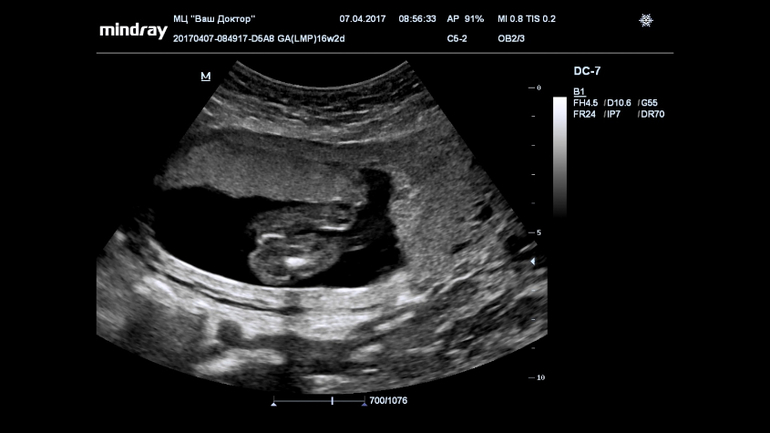

Ну девчуля же? Кто разбирается?

Пол малышаВсе 16 недель была просто уверенна, что в домике живет сыночка, а тут на УЗИ огорошили, что у нас там девица-красавица! Я конечно прибываю в небольшом шоке, но БЕЗУМНО этому рада!!!!!

Записали нам диск, все выходные пересматривала, сделала несколько фото, что скажете?